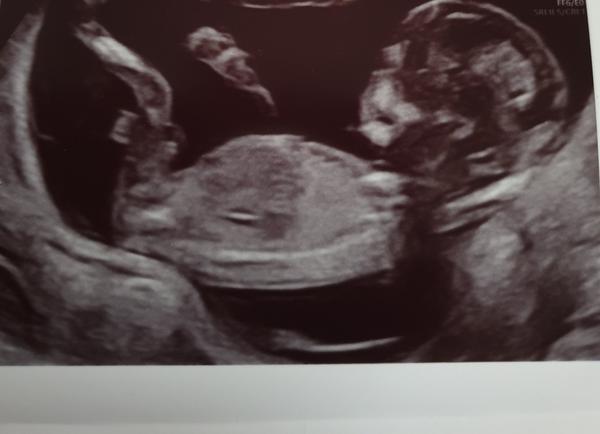

poznal byste pohlaví miminka?

Fotky jsou ze screeningu v trimestru a stáří miminka je 13+0.

bohužel z těchto fotografií se nic říci nedá. ☹